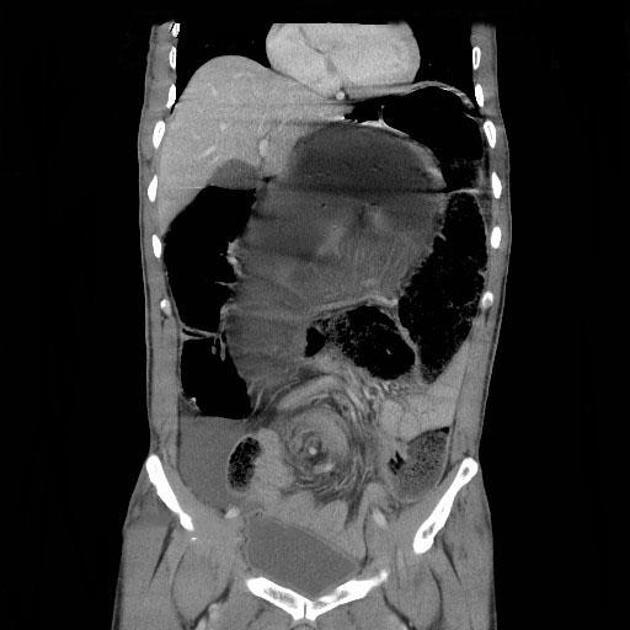

Imaging for volvulus sigmoid

• CT abdomen pelvis + IV contrast

• = very dilated sigmoid colon with whirl sign

• Also allows to check for bowel ischaemia, if ileocaecal valve is incompetent = signs of SBO